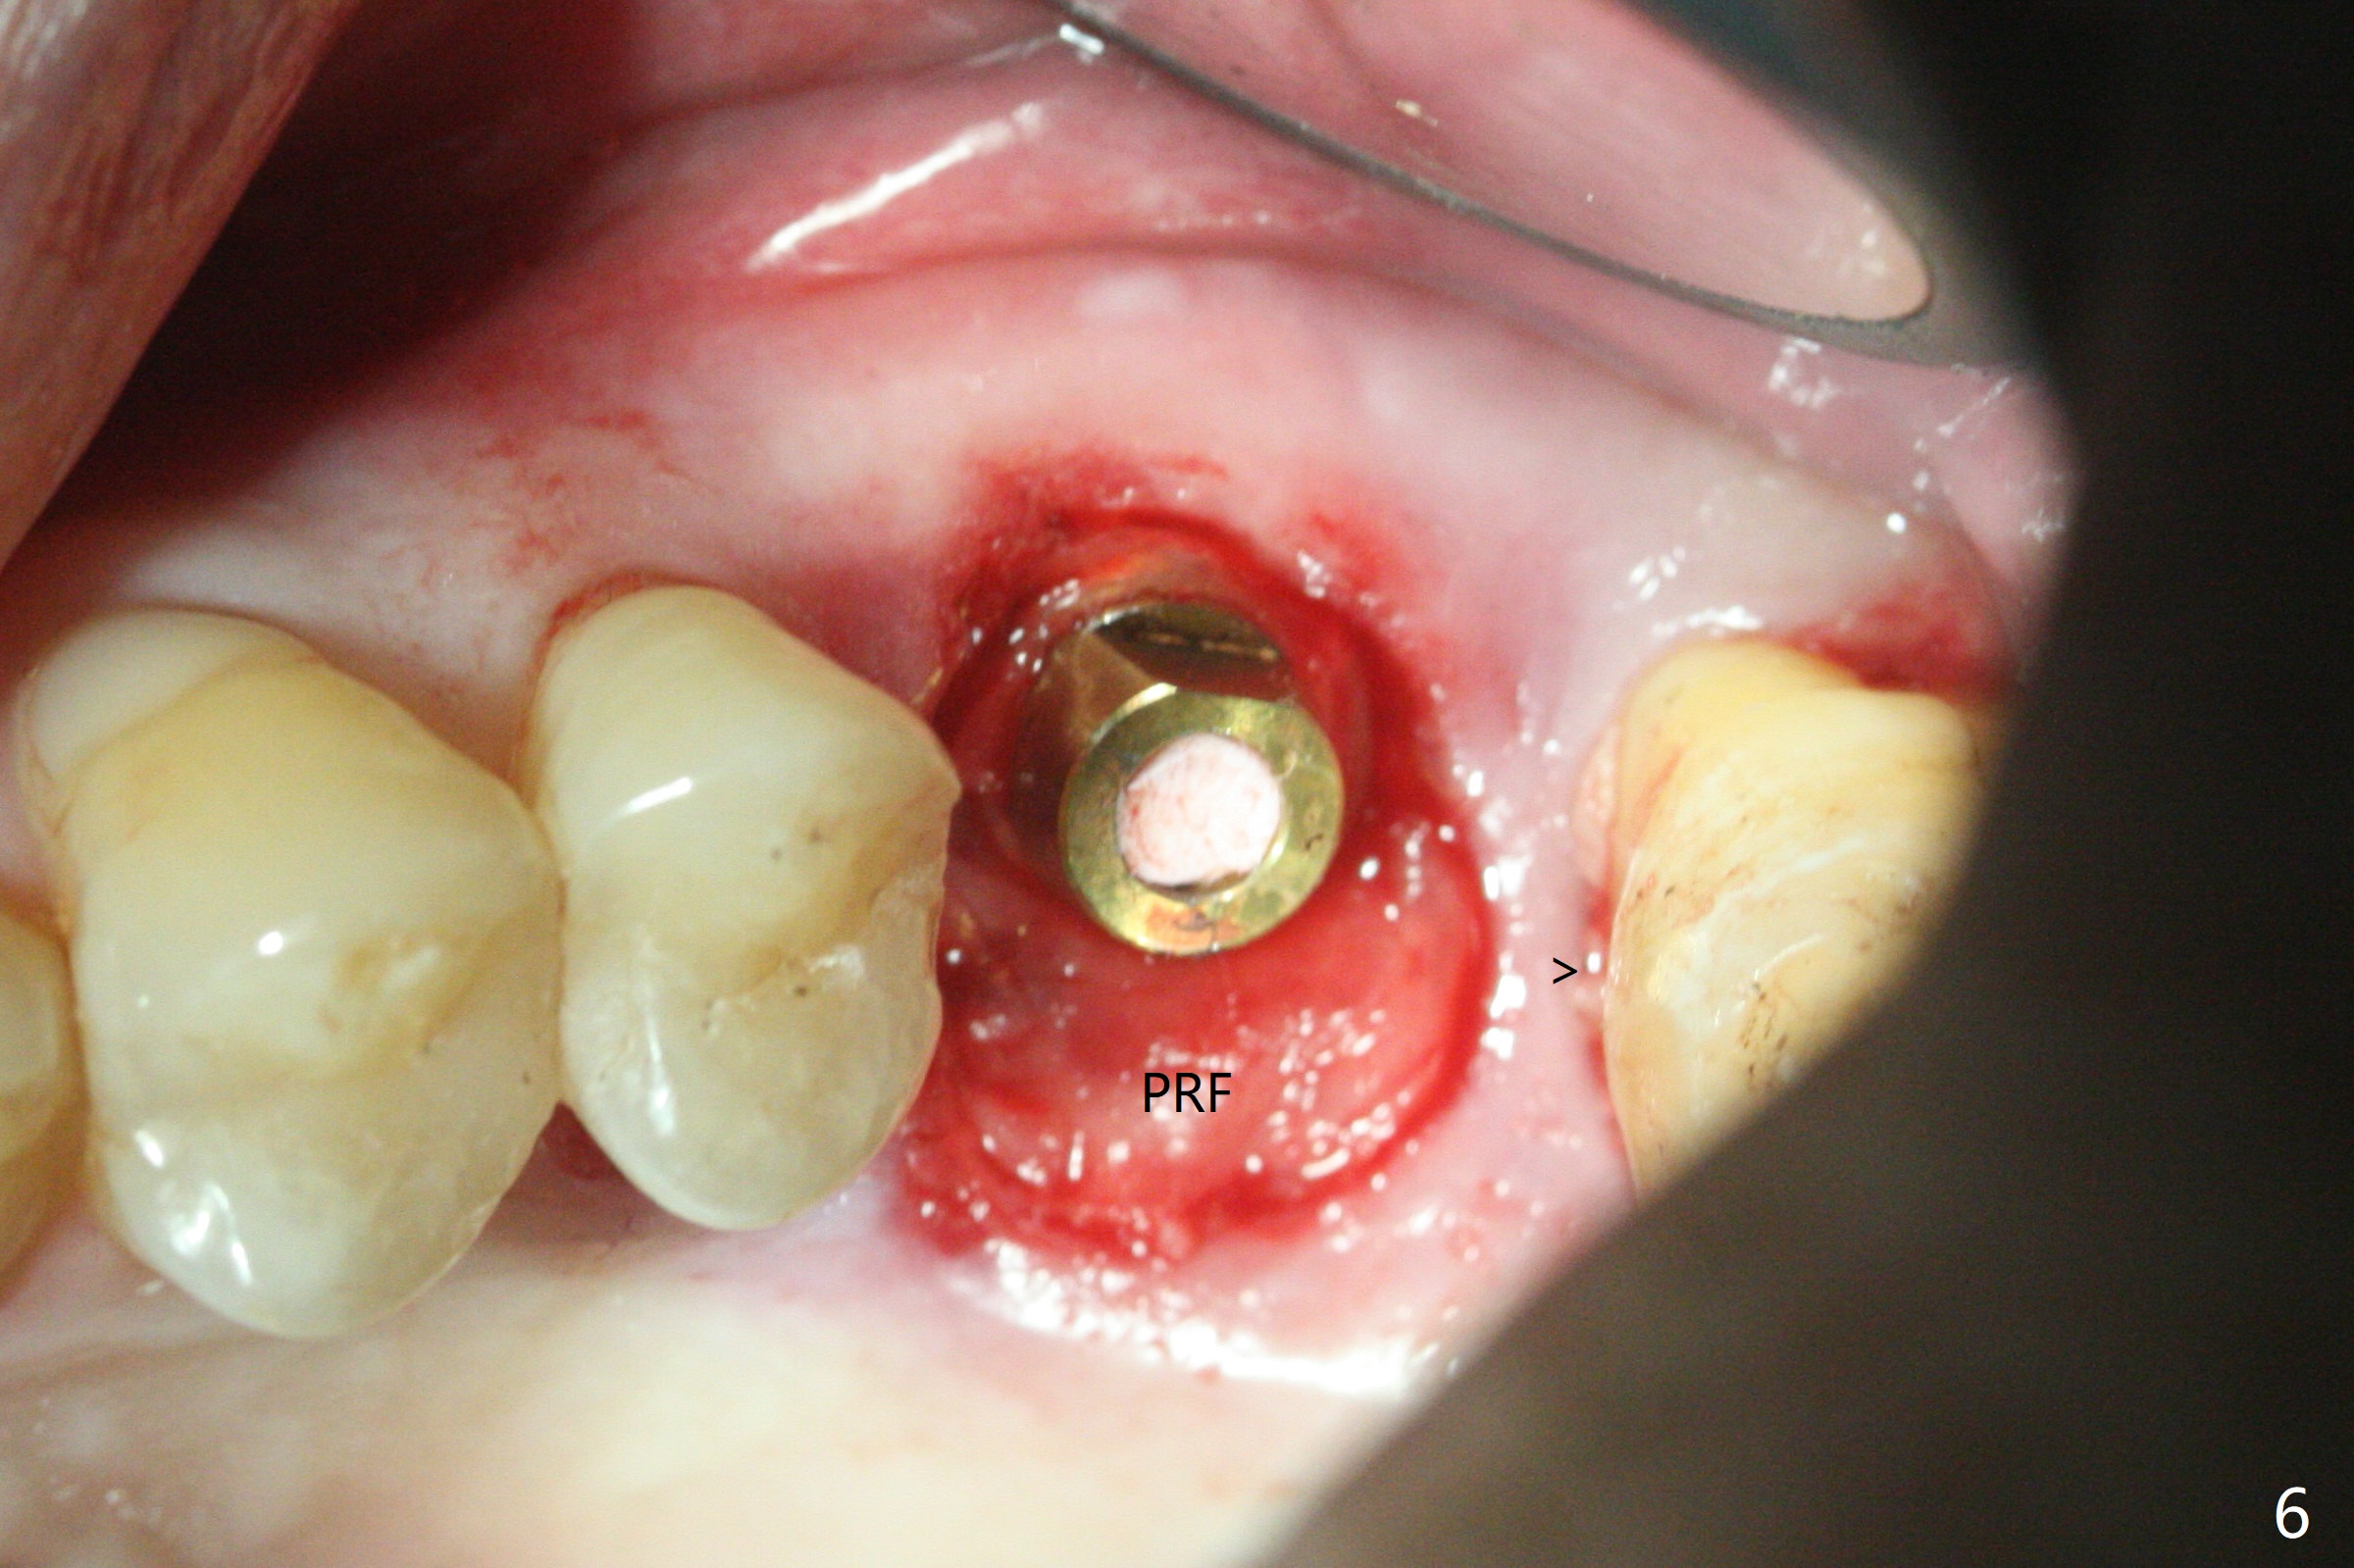

72岁男14号牙腭侧根尖接近上颌窦(图一,二:P),牙齿拔除后,根尖对刮治敏感,冲洗后,开始导板钻洞,圆钻穿透窦底,放置粘性骨粉和报废植体提升(图三:箭头)。放置小张PRF和骨粉(图四:箭头),植入正式植体,基台和骨粉(图五:*),最后覆盖PRF(图六),为了防止骨粉从邻牙牙龈沟(>)丢失,覆盖树脂敷料。基台和前后邻牙使树脂敷料术后一周巍然不动(图七:A)。术后一个月撤除树脂敷料,牙槽窝已经愈合(图八)。再过两周牙槽窝上皮好像进一步成熟(图九),然后塞入一个龈线,制备临时牙冠。